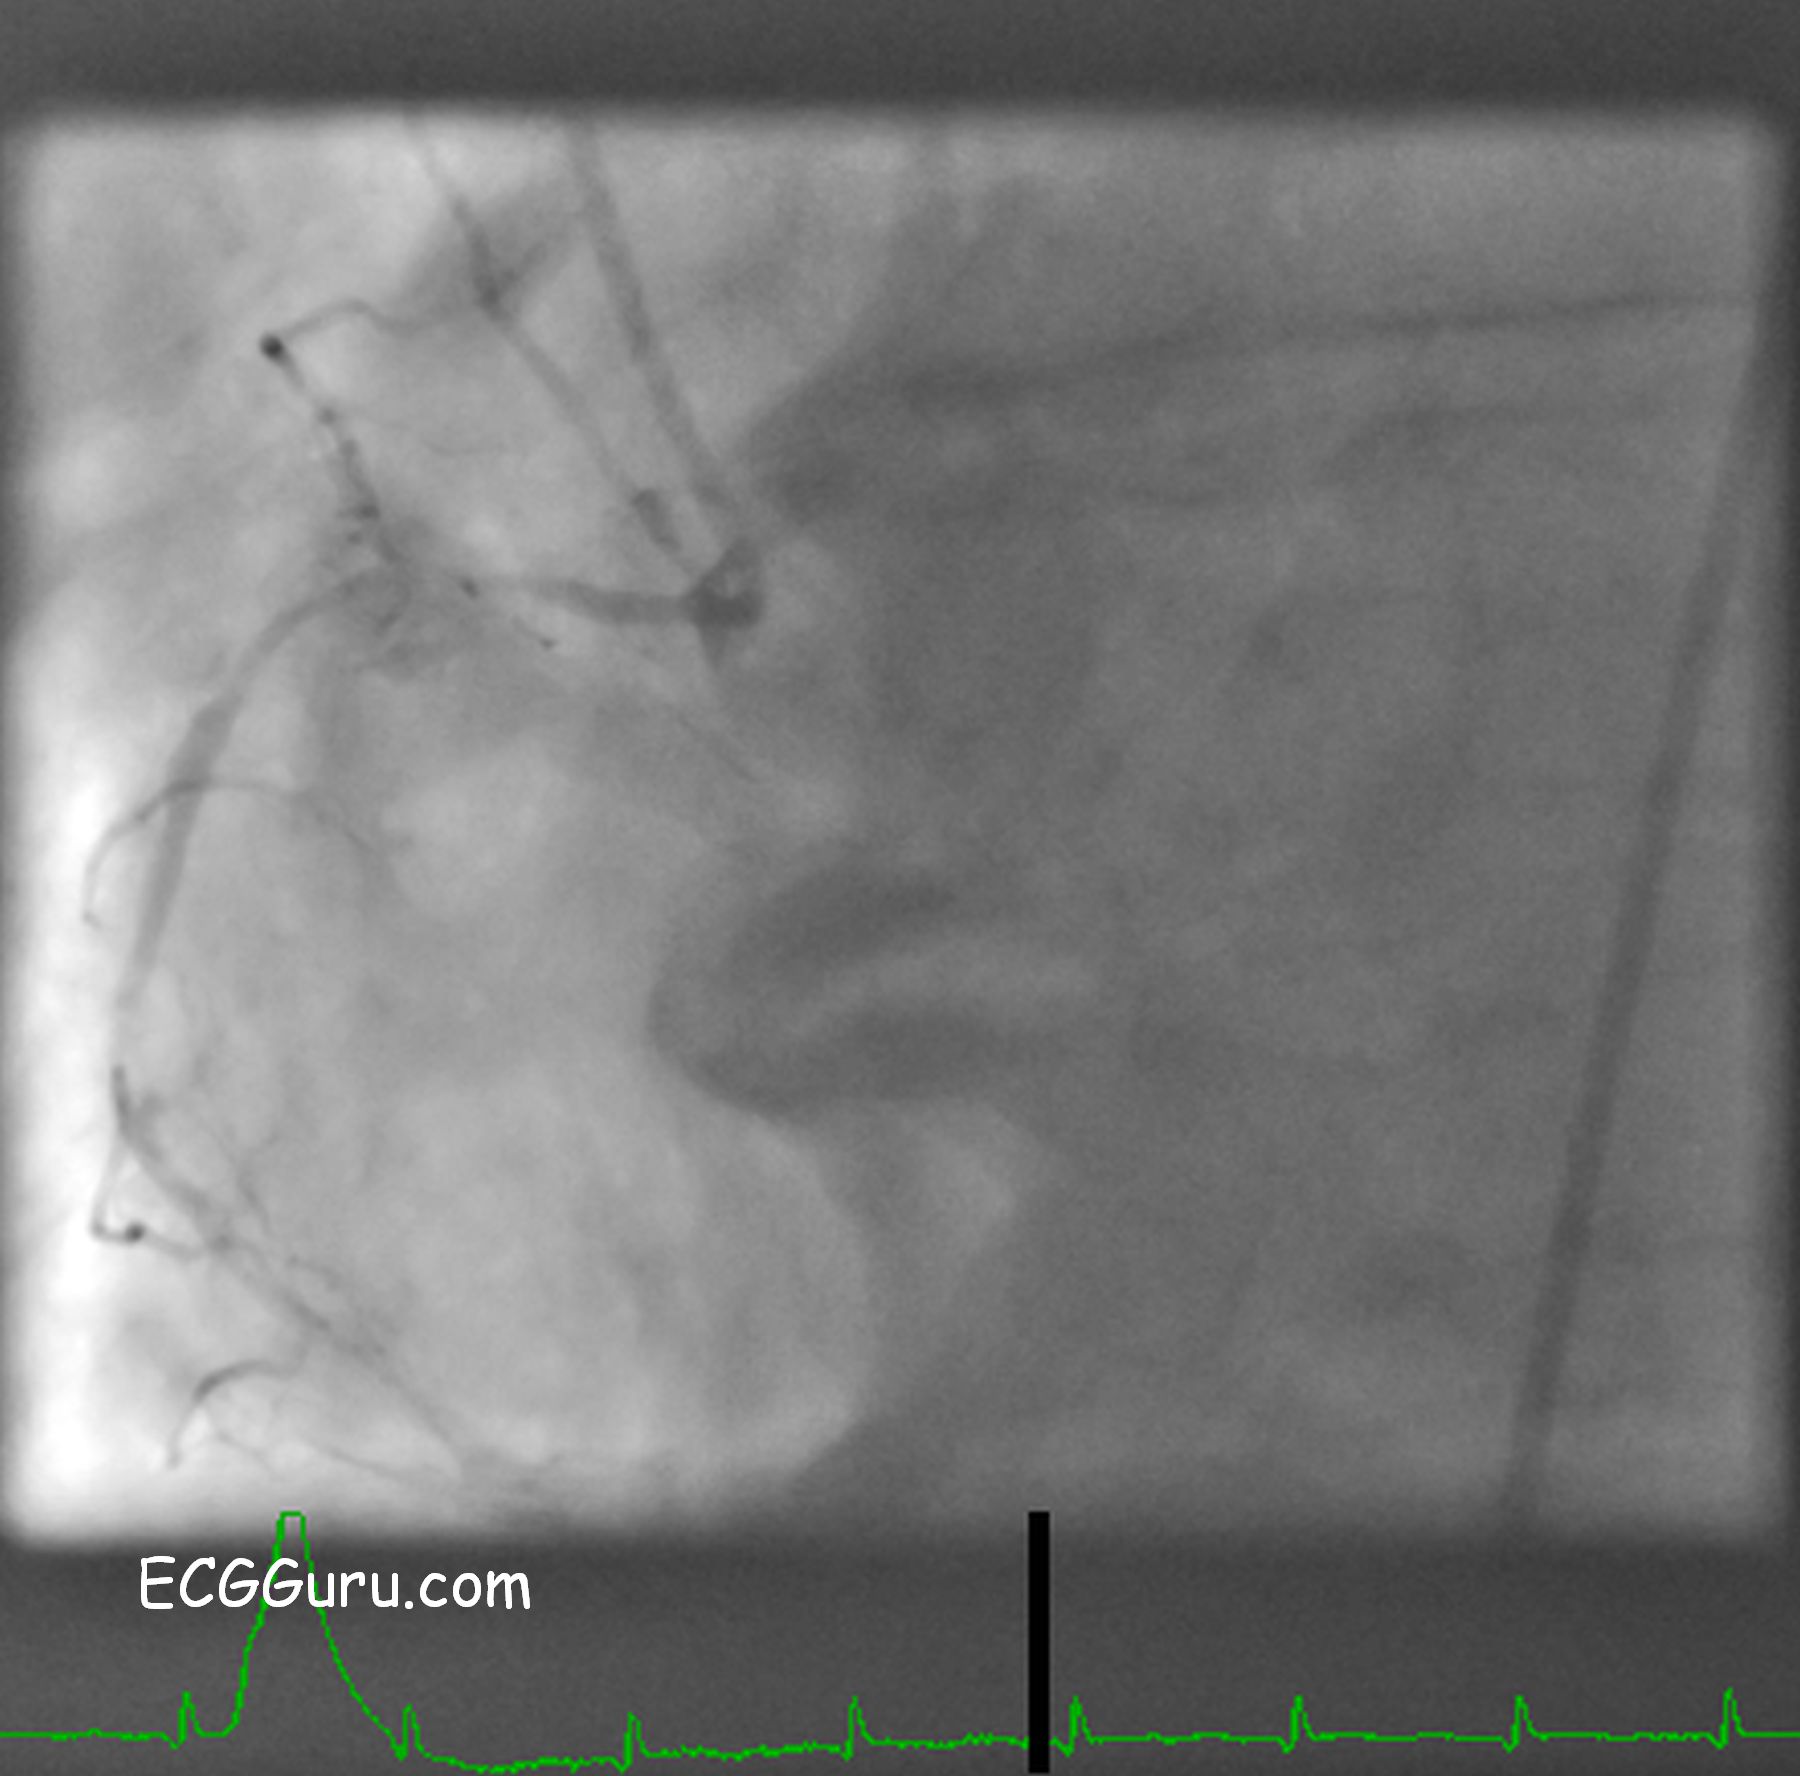

Non-dominant Right Coronary Artery In A Patient With A Dominant Circumflex Artery

Non-dominant right coronary artery

This is an angiogram of a non-dominant right coronary artery in a patient with a dominant left circumflex artery.  The RCA is very small, compared to the usual.  This patient is one of about 15 - 18% of the population whose circumflex artery perfuses the posterior/nferior wall of the left ventricle.

Click HERE to view the dominant circumflex artery of this patient.